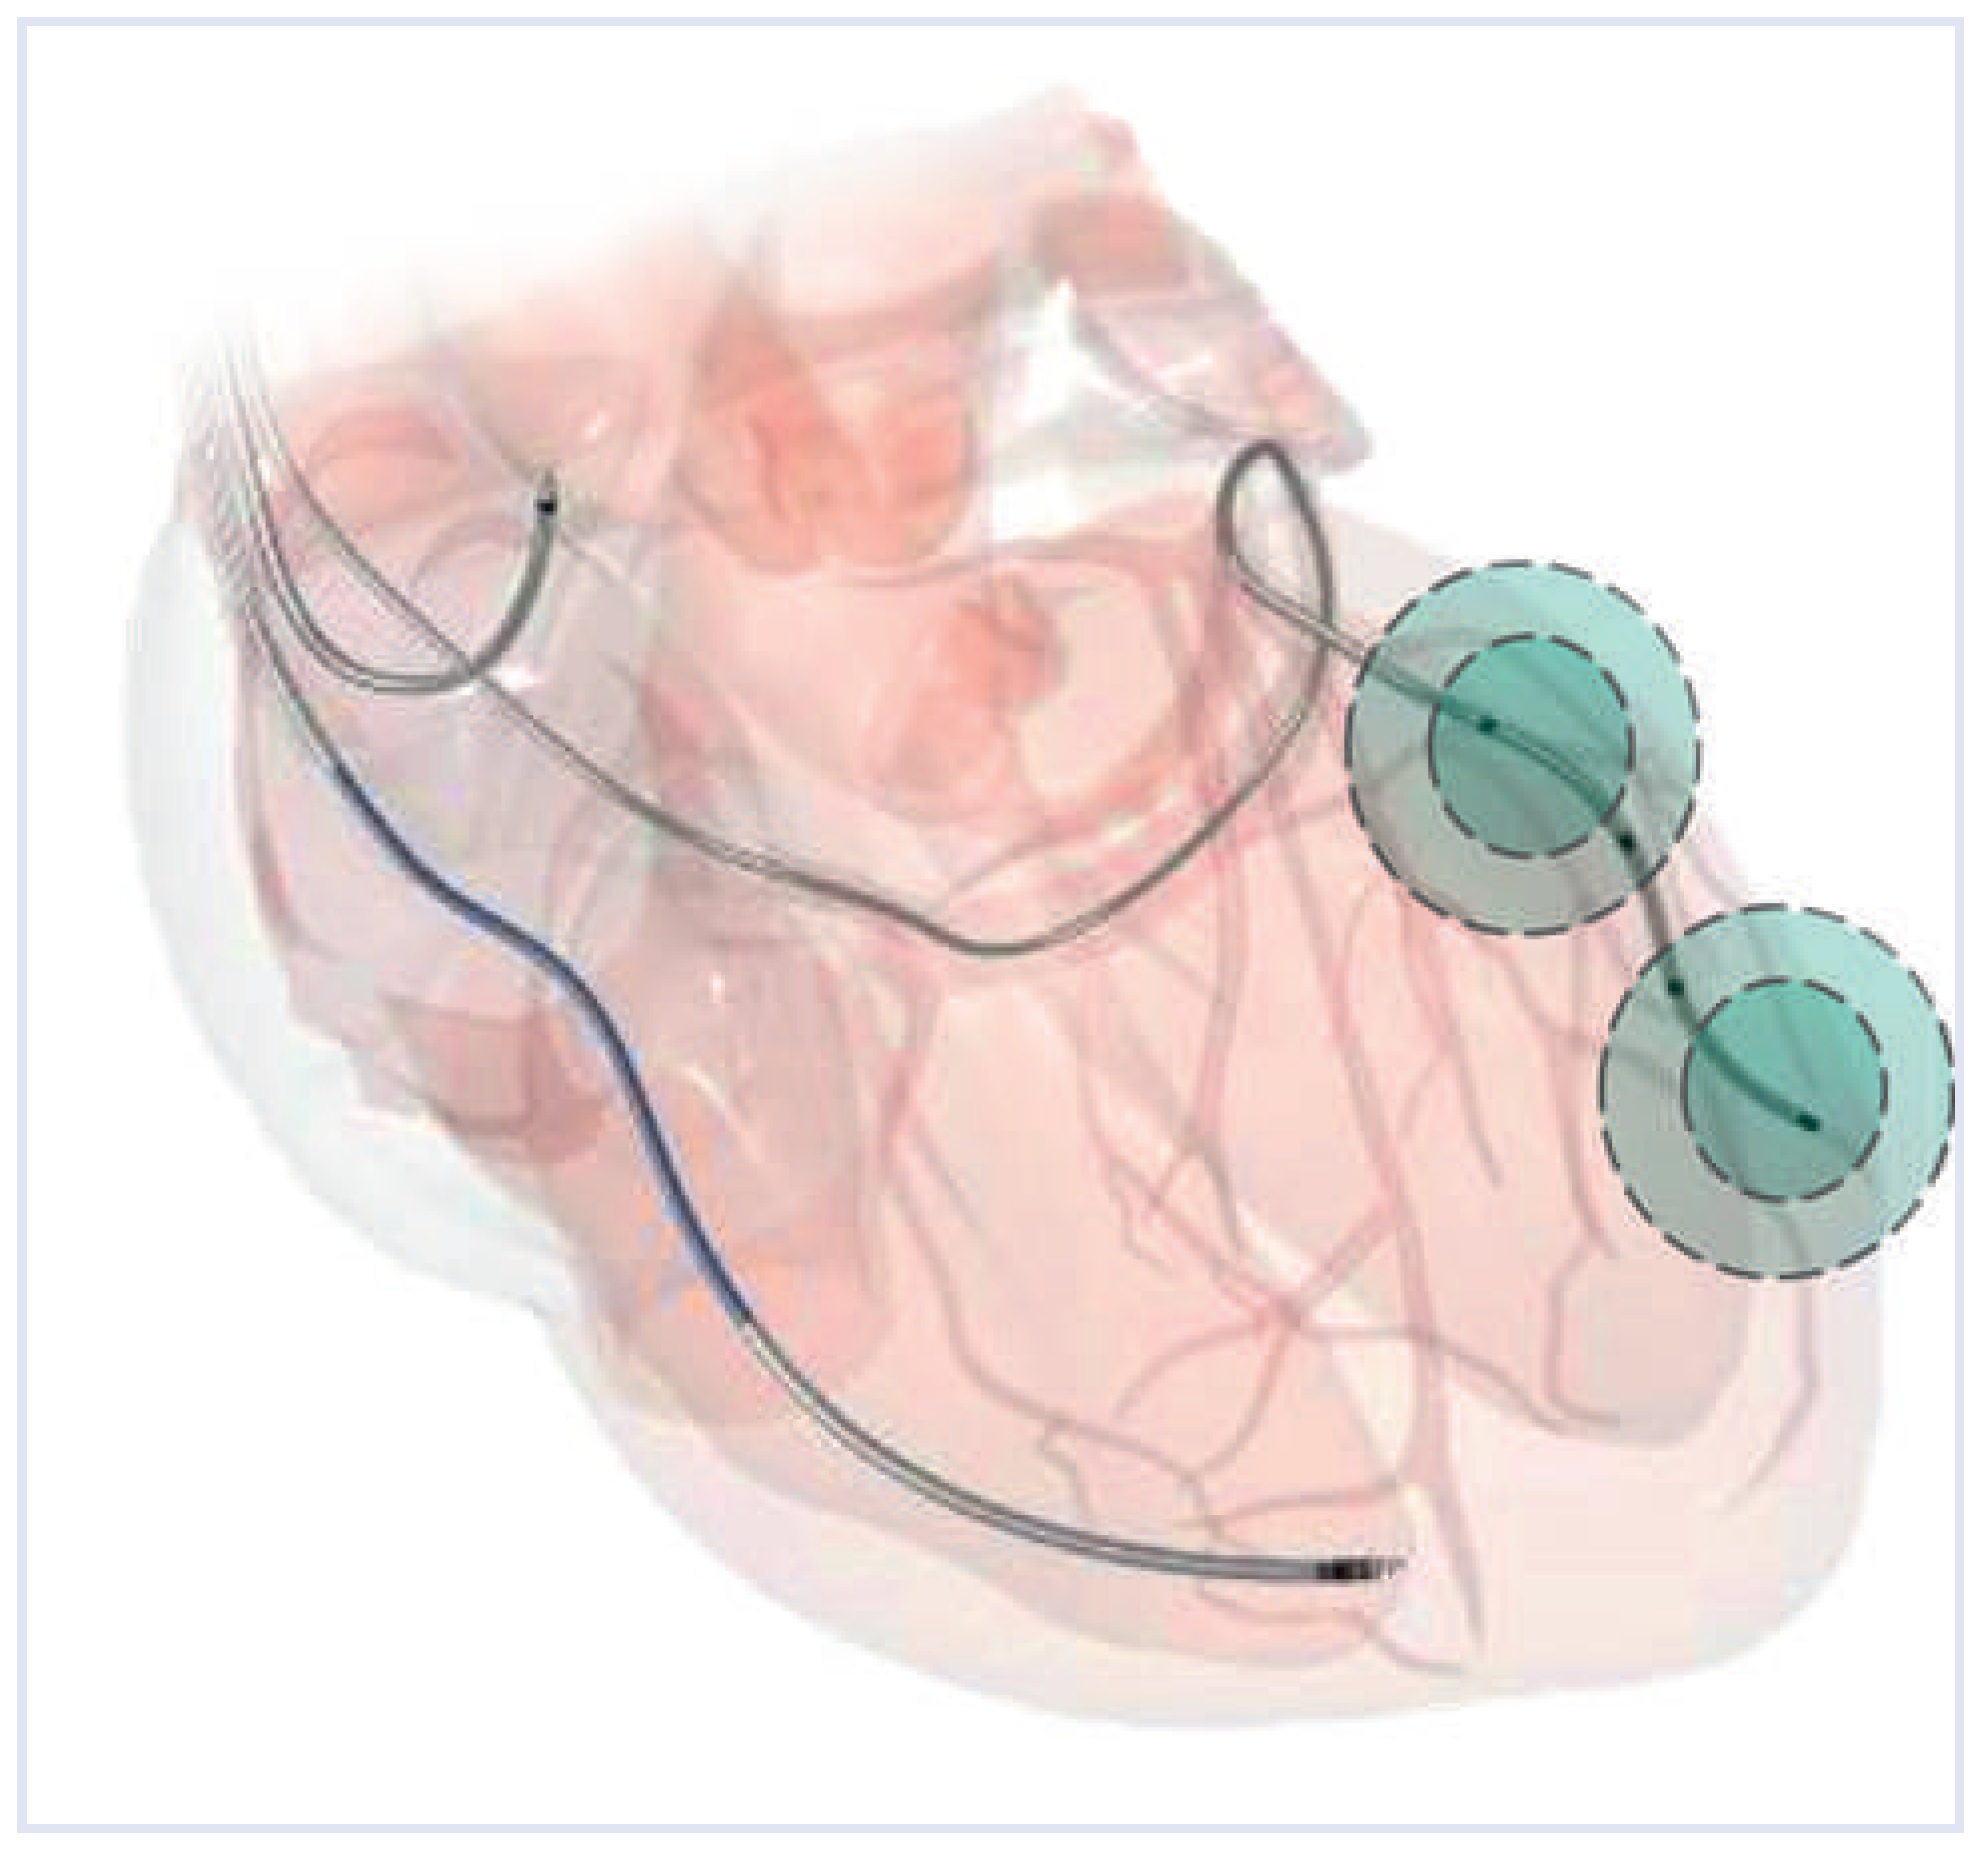

Die Suche nach Optimierungsmöglichkeiten der konventionellen CRT haben verschiedene Forschergruppen dazu gebracht, den Effekt der linksventrikulären Stimulation von mehr als einer Lokalisation zu untersuchen. Initiale Versuche erfolgten über die Positionierung einer zusätzlichen Elektrode, was jedoch zu Problemen eben durch Einlage einer zusätzlichen Elektrode führte [7,8,9]. Interessanterweise haben bereits publizierte Arbeiten gezeigt, dass die hämodynamische Antwort auf eine CRT allein durch empirische Veränderung des Stimulationsorts innerhalb eines Koronarsinusasts, ohne vorgängige Ausmessung der elektromechanischen Verzögerung – z.B. mittels Strain-Echokardiographie – verbessert werden kann [10,11]. Kürzlich wurde eine quadripolare (vierpolige) LV-Elektrode (Quartet model 1458Q, St. Jude Medical, Inc.) mit drei Ringelektroden (jeweils 20, 30, und 47 mm von der distalen Elektrode entfernt) entwickelt. Mit einem entsprechenden Aggregat der neuesten Generation (St. Jude Medical Quandra Assura mit MultipointTM Pacing) ist es nun möglich, von zwei Elektrodenpaaren der LV-Elektrode, zusätzlich zur RV-Elektrode, ein grösseres LV-Areal zeitgleich oder leicht zeitversetzt zu erregen (Abb. 1).

Abbildung 1. Eine neue Möglichkeit der kardialen Resynchronisationstherapie stellt das sog. «Multisite Pacing» dar. Über ein zusätzliches Elektrodenpaar einer 4-poligen transvenös eingelegten linksventrikulären (LV-)Elektrode in einen Ast des Koronarsinus kann simultan an drei verschiedenen Orten der Ventrikel stimuliert werden. (Abdruck mit freundlicher Genehmigung von St. Jude Medical).

Bis zu 30% der Patienten sprechen nicht auf die bisherige CRT an (sog. «Non-Responder»). Um dies zu verbessern, wurde kürzlich das sog. «Multisite Pacing», also die simultane linksventrikuläre Stimulation von zwei Positionen entwickelt. Ein entsprechendes CRT-Device (Unify Quadra MP™ oder Quadra Assura MP™ CRT-D) ist durch ein Software-Upgrade in der Lage, via einer quadripolaren (vierpoligen) transvenös eingelegten Elektrode von jeweils zwei Elektrodenpaaren der LV-Elektrode zusätzlich zur RV-Elektrode simultane Stimulationsimpulse abzugeben, um so synchron ein grösseres LV-Areal erregen zu können (Abb. 1).